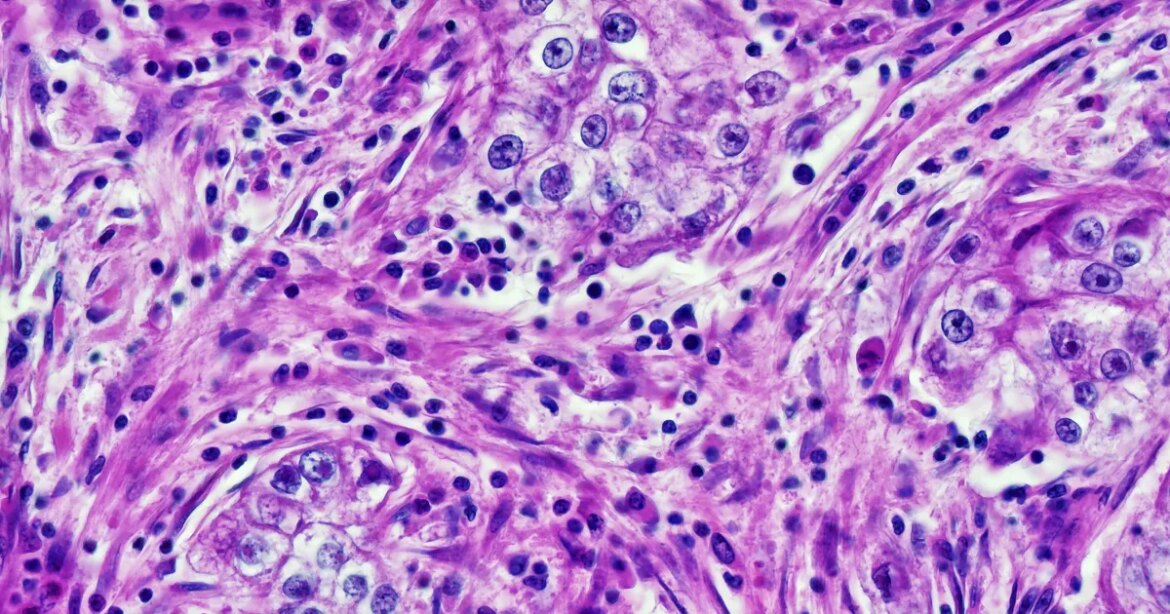

there were surprising findings published in the journal cell report medicineShows that four major AI-augmented pathology diagnostic systems vary in accuracy depending on patients, The disturbing thing is that AI is extracting demographic data – age, gender and race – directly from pathology slides, a feat that is impossible for human doctors.

To conduct the study, Harvard University researchers combed through nearly 29,000 cancer pathology images from approximately 14,400 cancer patients. Their analysis found that deep learning models displayed worrying biases 29.3 percent of the time — in other words, on about a third of all diagnostic tasks assigned to them.

To give a concrete example, AI tools were able to specifically identify samples taken from black people. The authors wrote that these cancer slides had higher numbers of atypical, neoplastic cells and fewer supporting elements than white patients, allowing the AI to eliminate them, even though the samples were anonymized.